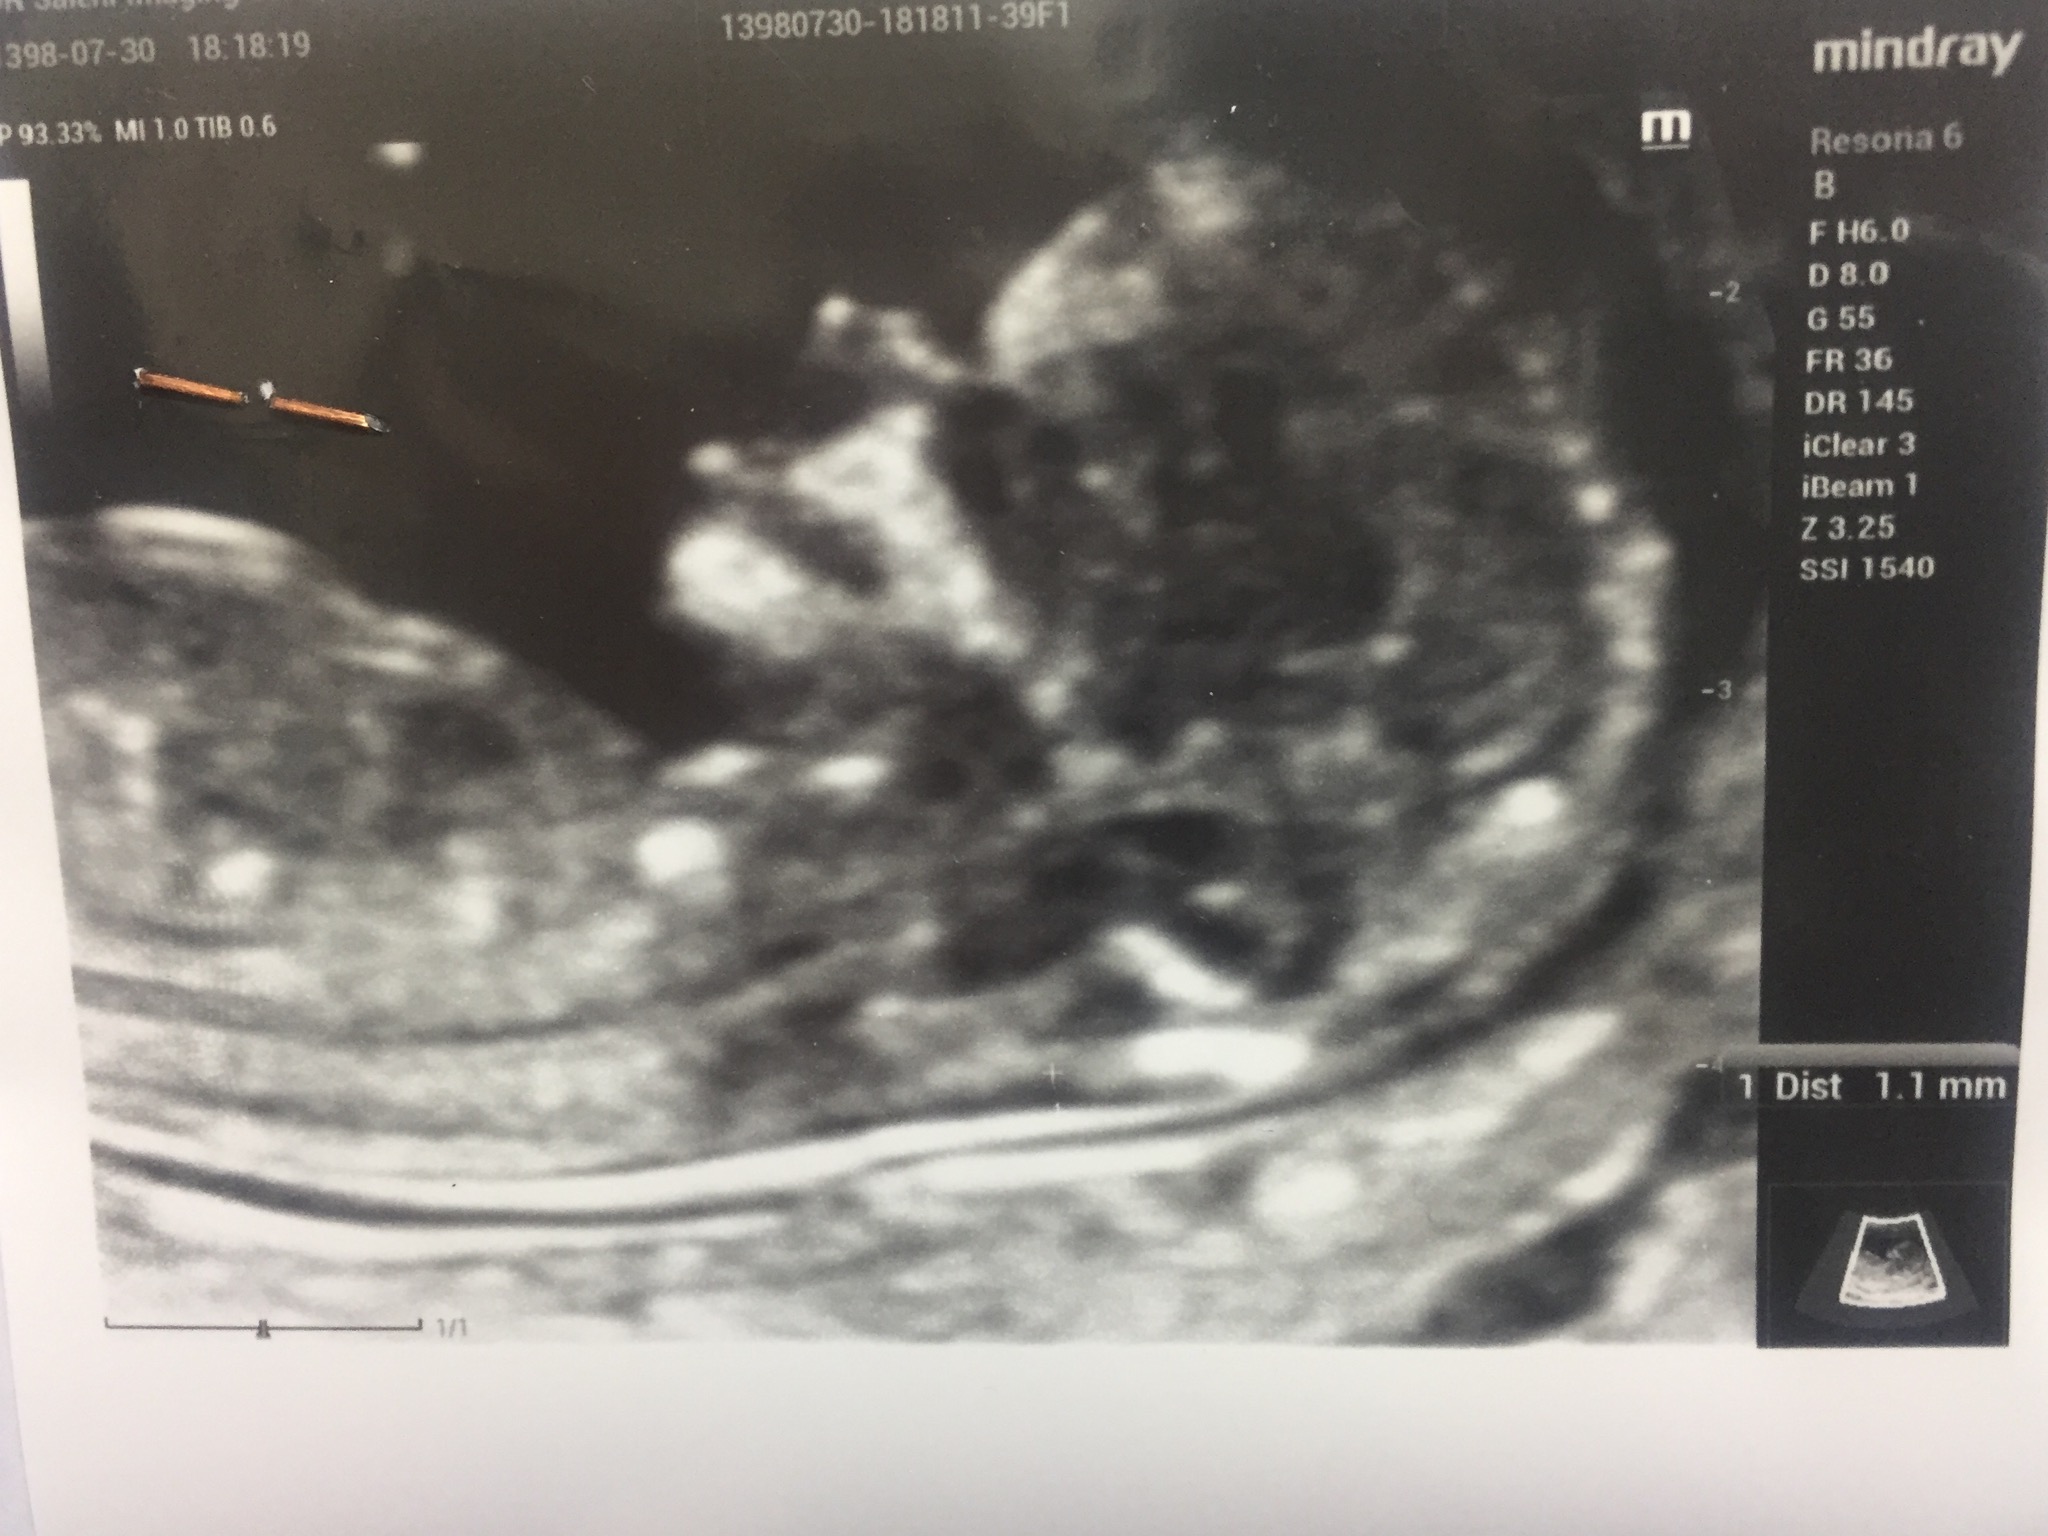

تعیین جنسیت